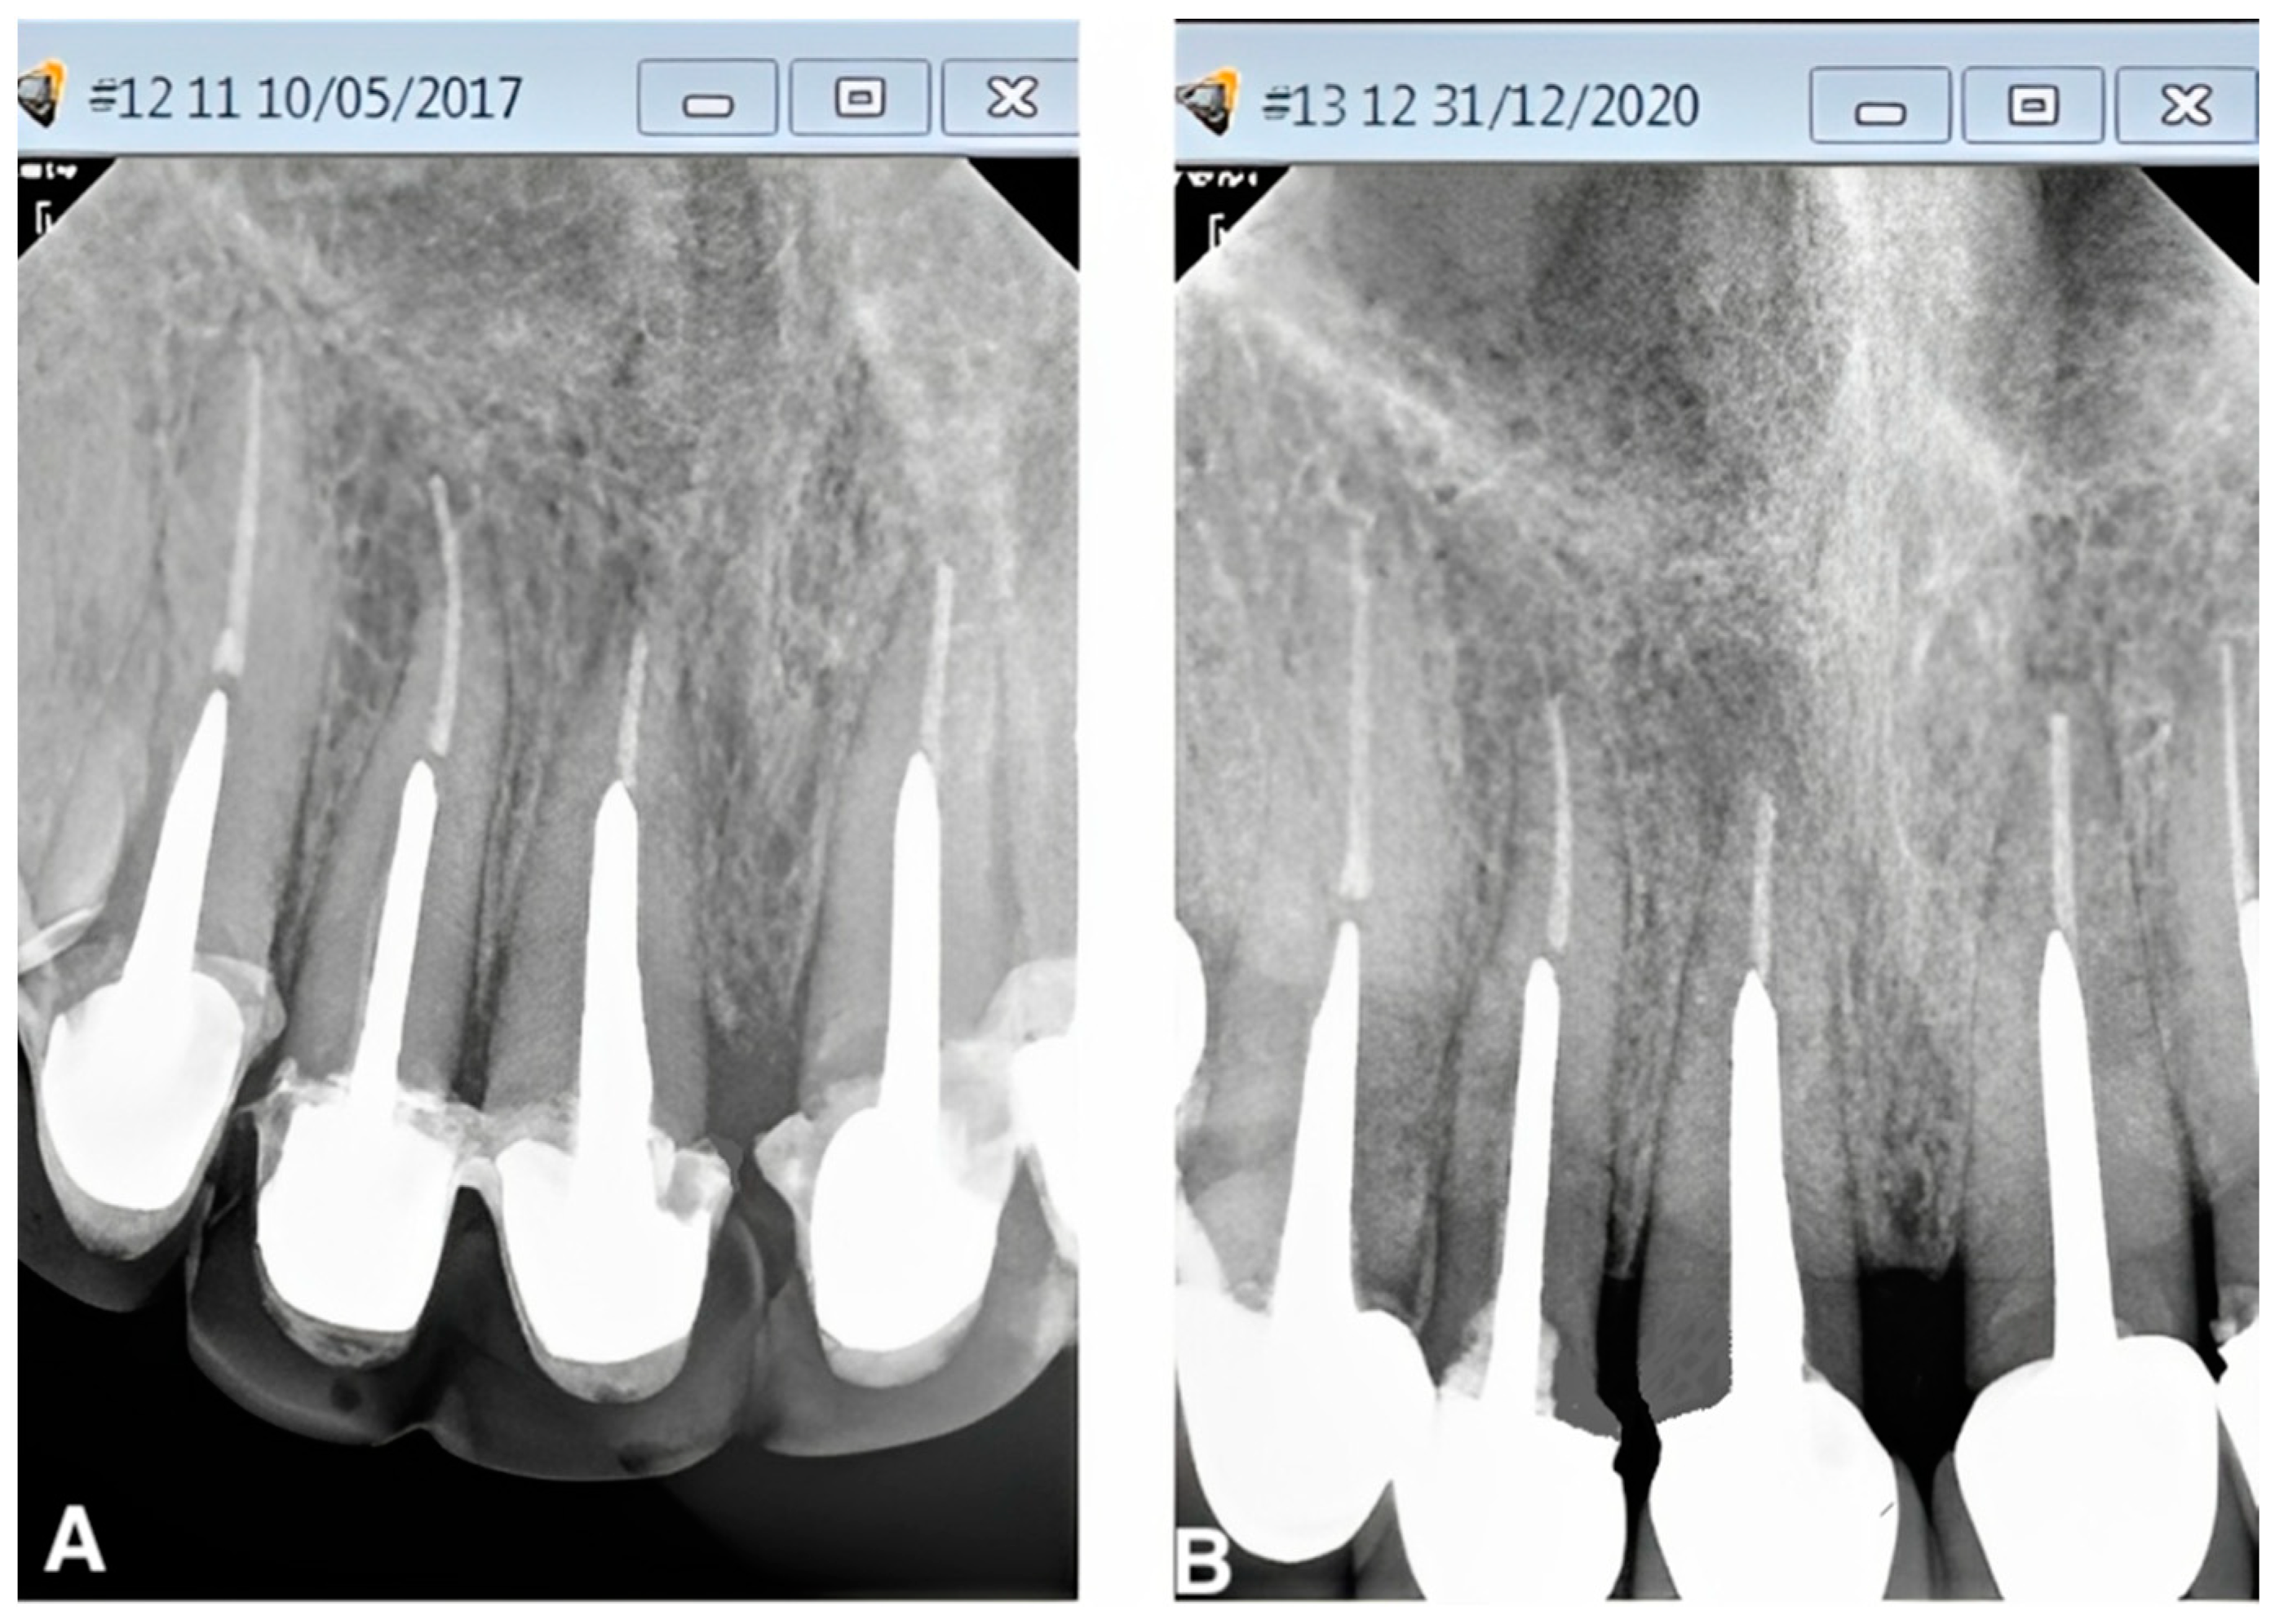

A healthy periapex PAI 1 was described as a healthy periapex, which had the normal width of permanent ligament space and surrounding bone that looked normal. The evaluation of all other PAI scores (2,3,4,5) was mentioned as apical periodontitis. The chi-square test was employed for statistical analysis, with a significance level of p < 0.05. Out of 70 recalled patients, the male students had performed a total of 20 post and core treatments, whereas the female undergraduate students had completed post and core treatments for 50 cases. A total of 90% (n = 18) of the teeth in group I with no gap between the residual gutta-percha and the post were found to be healthy, while 10% (n = 2) were found to be diseased (Figure 1). In group II, there were 66.7% (n = 22) of normal teeth and 33.3% (n = 11) of diseased teeth, with a gap of more than 0 mm to less than 1 mm between the post end and the remaining gutta-percha (Figure 2). However, 58.8% (n = 10) of group III patients with a gap of more than 1 mm between the post end and the remaining gutta-percha were found to be healthy, whereas 41.2% (n = 7) were found to be diseased. (Figure 3). A total of 32% (n = 16) endodontically treated teeth were found diseased and treated by the female students while 68% (n = 34) of teeth were found normal. A total of 20% (n = 4) endodontically treated teeth were found diseased and treated by the male students while 80% (n = 16) of teeth were found normal. (Figure 4 and Figure 5) The quadrant wise treated teeth included for follow up examinations were 36 maxillary anteriors, 8 maxillary posteriors, 12 mandibular anteriors, and 14 mandibular posteriors. Among the maxillary anteriors, 69.4% (n = 25) of teeth were found normal however 30.6% (n = 11) of teeth were found diseased. Among the maxillary posteriors, 50% (n = 4) of teeth were found normal however 50% (n = 4) of teeth were found diseased. Among the mandibular anteriors, 83.3% (n = 10) of teeth were found normal however 16.7% (n = 2) of teeth were found diseased. Among the mandibular posteriors, 78.6% (n = 11) of teeth were found normal however 21.4% (n = 3) of teeth were found diseased. (Figure 4 and Figure 5).

Figure 3. (A,B). Peri-apical radiograph in Group III (gap of >1 mm between cemented post and remaining gutta-percha) showing the PAI status, before and after 4 years with periodontal inflammation and bone loss (red circle) of follow up using the CS-R4 program.